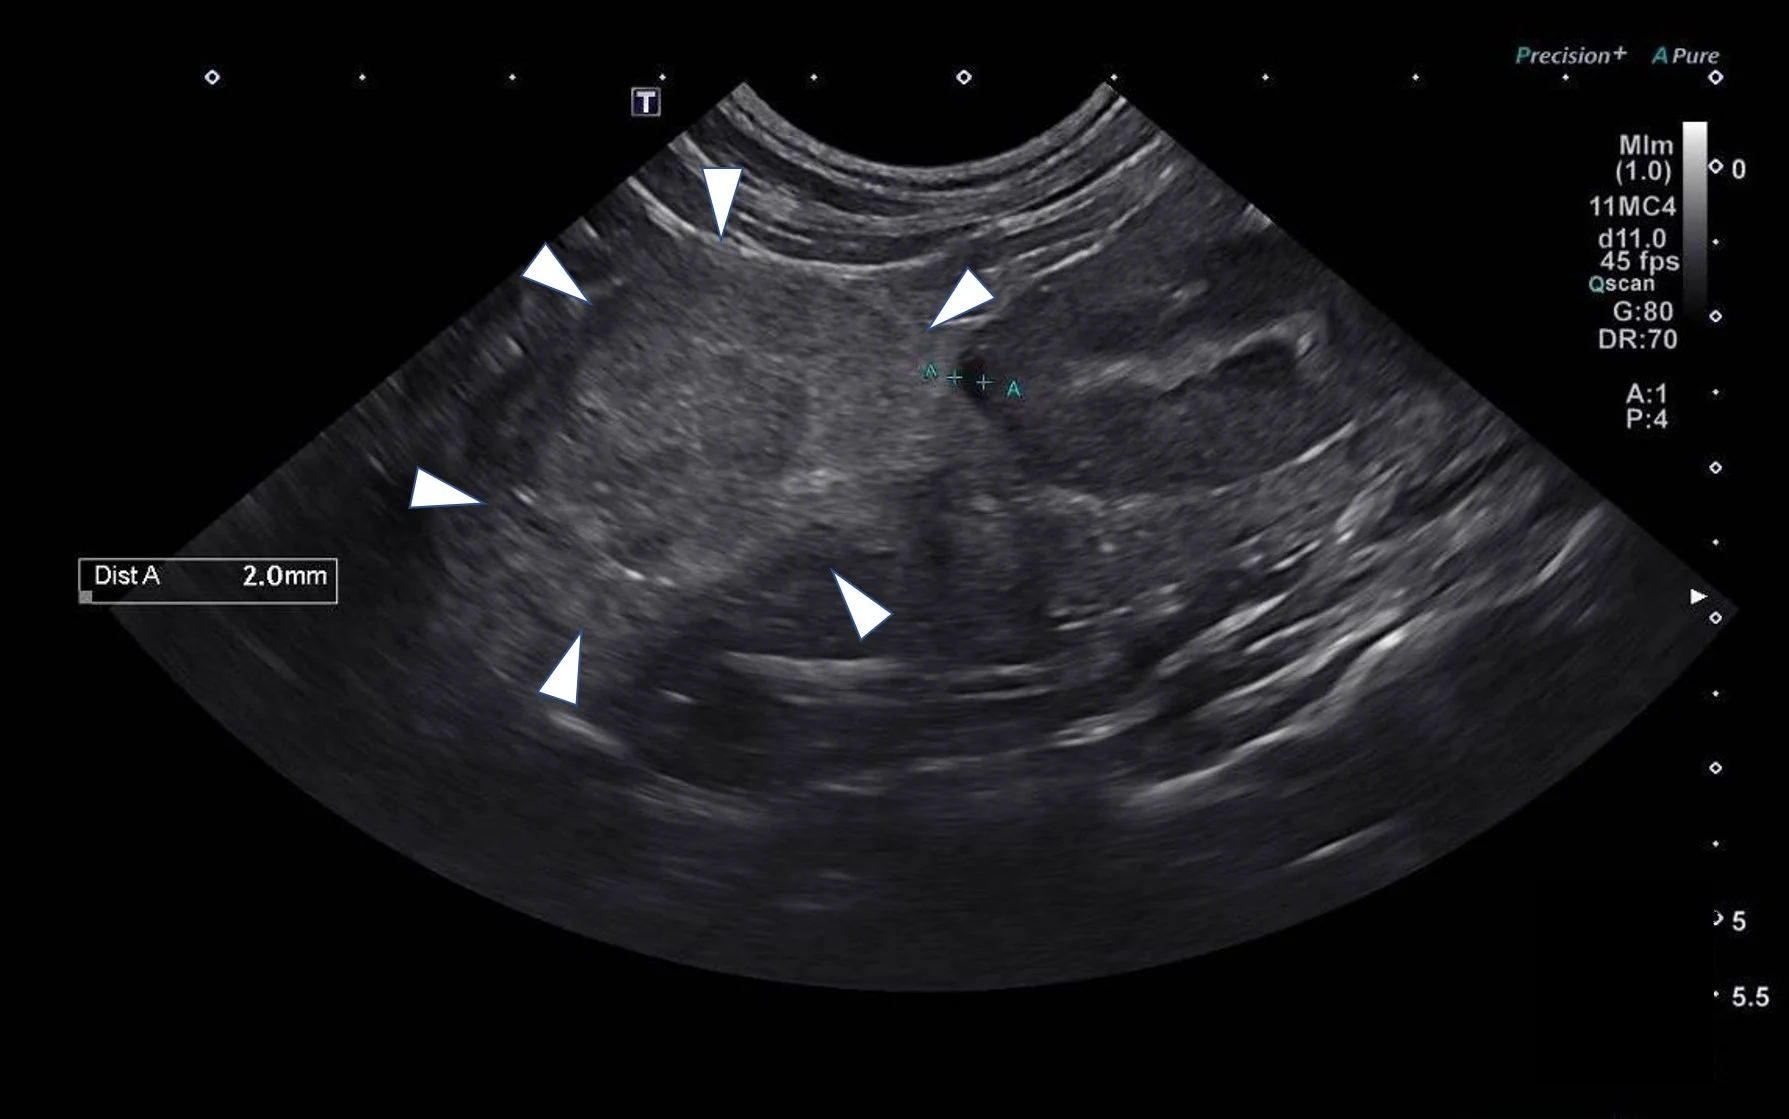

Radiographic findings were an indication for advanced imaging of the abdomen. Based on the available modalities, ultrasonography was elected so the procedure could be performed promptly without placing the patient under general anesthesia. Ultrasound results showed an enlarged right adrenal gland (Figure).

Abdominal ultrasound showing a 4.2- × 3-cm mass involving the right adrenal gland (arrowheads)

Ultrasound findings, along with other clinical and laboratory results, suggested Sparta had an aldosterone-producing adrenal tumor causing primary hyperaldosteronism.1 Hyperaldosteronism is characterized by hypokalemia (secondary to potassium-wasting effects of aldosterone) and severe hypertension (secondary to sodium-mediated volume expansion).1,2 Serum aldosterone was subsequently measured from a sample collected at presentation and found to be markedly elevated (>187.4 ng/dL; reference interval, 7-14 ng/dL).